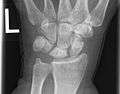

Left hand x-ray with Kienbock's Disease showing 4 mm negative ulnar variance and Kienbock's Disease Stage IIIB